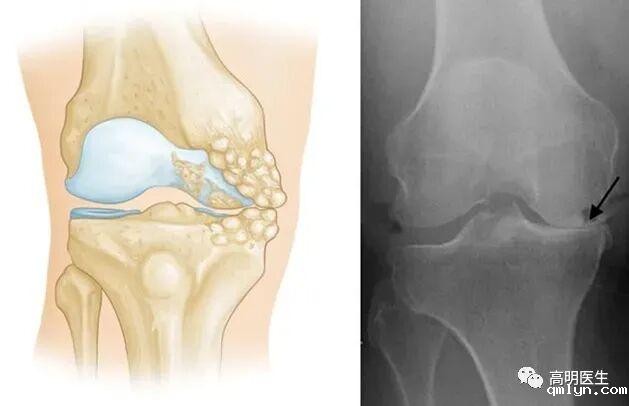

关节炎不是冻出来的

· 骨关节炎:最常见的类型,主要由关节软骨的退化引起。年龄增长、肥胖、过度使用关节、遗传因素等才是主要发病原因。

关节就像汽车轮胎,也有“使用寿命”。随着年龄增长,关节软骨逐渐磨损,弹性下降,最终出现骨赘(俗称“骨刺”),这就是骨关节炎的过程 。 只不过有些人的关节耐磨,有些人的不耐磨罢了。不仅人类,几乎所有脊椎动物都会得骨关节炎,但是对于一些关节负荷极小的动物(如蝙蝠、树懒等)发病率极低。这也说明骨关节炎是关节对磨损的自然反应。